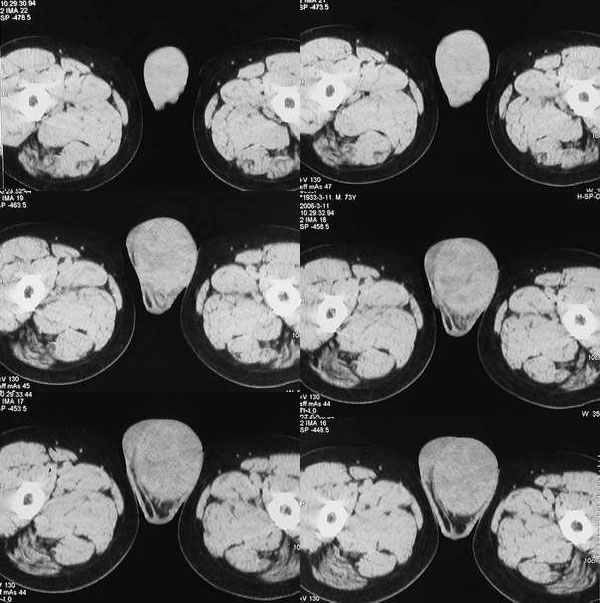

男 73 睾丸肿块3月,病人不原增强.直接手术

睾丸体积增大,轮廓光整,内部密度不均匀,双侧腹股沟未见异常

--------睾丸精原细胞瘤常见。

手术结果 睾丸精原细胞瘤